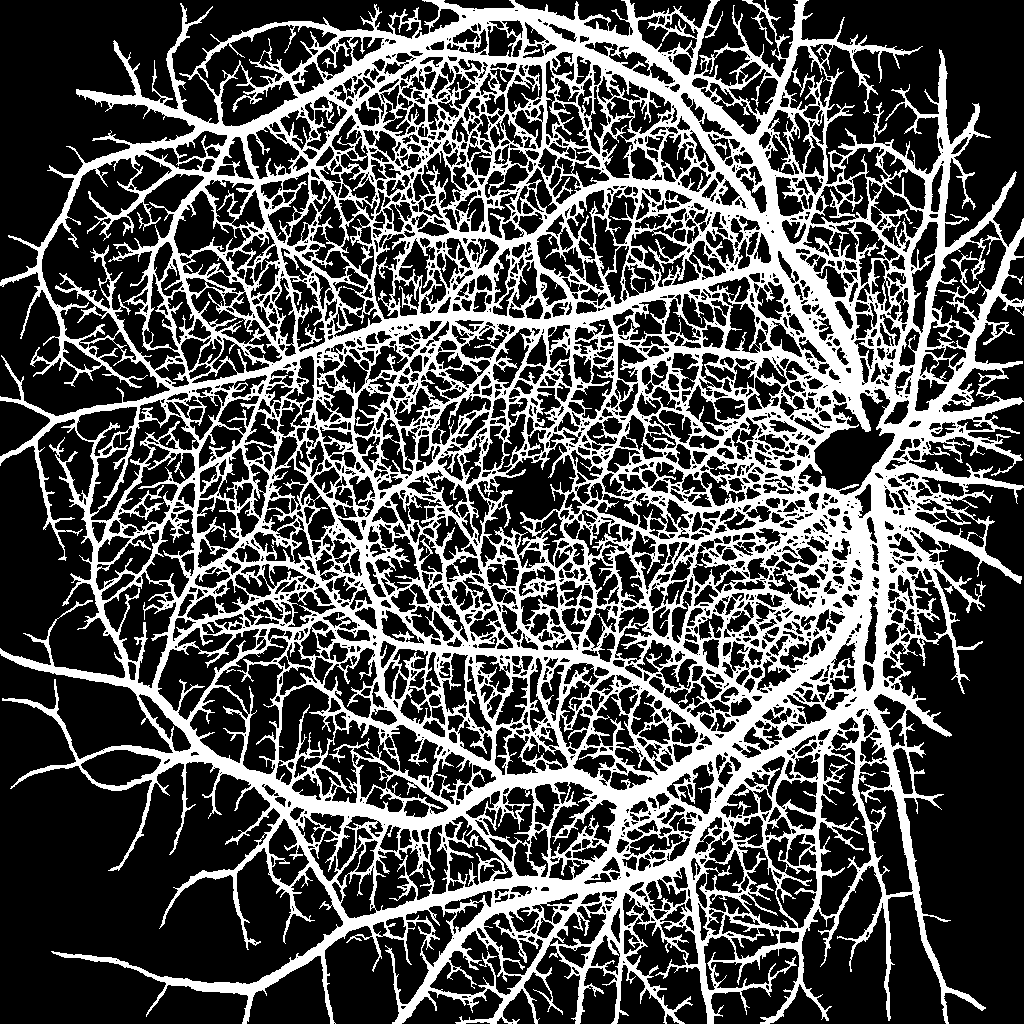

Diabetic retinopathy causes retinal vascular changes, and while being subtle at first, it eventually leads to dangerous vascular abnormalities and neovascularization. We hypothesize that by explicitly feeding the segmentation map of the vasculature to a deep neural network, we can provide a strong inductive bias for the network to predict the severity of DR. Recent studies suggest that early DR progression is mainly correlated with biomarkers found in the deep vascular complex (DVC), while the superficial vascular complex (SVC) is generally only affected in severe cases [1, 6]. The authors hypothesize that the DVC might be more susceptible to ischemic damage because of its anatomical proximity to the outer plexiform layer, which has a high oxygen consumption. Therefore, it becomes clear that including small capillaries in the segmentation map is vital. However, to our knowledge, there is no publicly available dataset of OCTA images with corresponding vessel segmentation that includes small capillary vessels. Merely two public datasets, namely OCTA-500 and ROSE, have been released with segmentation labels for vessels and the foveal avascular zone (FAZ), both of which unfortunately only segment the largest vessels of the SVC [7, 8]. To circumvent the problem of missing labeled data, we generate an artificial dataset ourselves. Figure 1 shows our proposed pipeline.

In our work, we investigate whether an additional input channel to our network can boost the performance of a neural network. Our proposed additional input is a segmentation map of the vasculature, including small capillaries in the retina. To extract a faithful segmentation, we use synthetic OCTA images to train a segmentation network, which can then be used to generate the additional input channel on the fly.

Instead of limiting bias fields to the outer rings of the FOV, we randomly apply them at every possible position as part of data augmentation. Furthermore, we employ random rotation, flipping, elastic transformation, scaling, and motion artifacts during the training of the segmentation network. We use a variation of the very successful U-Net architecture [18] and follow the guidelines of nnU-Net to configure our network optimally for the given task [19].

2.2 Task A: Lesion Segmentation

We define the segmentation task as a multi-label classification problem, where each pixel can be part of the classes IRMA, NA, NV, or neither. We choose the widely successful U-Net architecture, which is known for its reliable segmentation performance on medical image datasets [20, 19]. For the optimal training parameters, we follow the guidelines of nnU-Net that define preprocessing steps, network architecture, loss function, and learning rate. Our final architecture can be seen in Figure 3, where for our baseline model, for the network using the additional segmentation map input, and . Our loss function is the sum of the soft Dice loss and the channel-wise binary cross entropy loss.

Because of the small dataset and large class imbalances, we observe strong overfitting right from the start. We, therefore, apply extensive data augmentation, such as elastic deformation, contrast changes, Gaussian smoothing, flipping, and rotation. To further reduce overfitting, we initialize our proposed network with the weights from the pre-trained vessel segmentation network. We then train a baseline system as well as our proposed method for 300 epochs and select the checkpoint with the highest Dice similarity coefficient (DSC) on the validation set.

Instead, we focused on testing the idea of integrating synthetic data into the prediction life cycle. We successfully extended Menten et al.’s work to generate OCTA images for ultra-wide scans. Using our training method, we can segment tiny capillaries whose diameter is similar to the physical resolution of the OCTA scanner. On this dataset, we could not find any significant improvement using the segmentation maps as input. However, we consider this finding relevant, as it indicates that the baseline models are strong enough to extract that information by themselves. It would be interesting to see whether this method could benefit from a larger image corpus, where networks are less prone to overfitting.